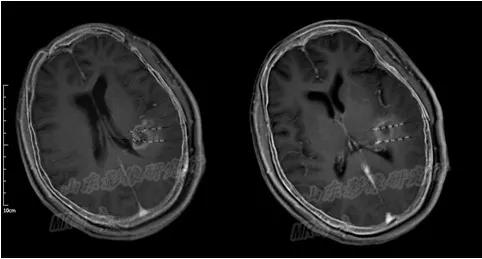

磁共振图清晰显示了满女士手术后复发病变情况

术前TPS计划

术后24小时内MRI/CT图像融合

MR/CT融合图像解决了I125放射性粒子在磁共振图像上显示不清、CT图像病灶轮廓勾画

困难的缺点,达到精准的病灶与粒子的空间分布显示,有利于术后的TPS验证。